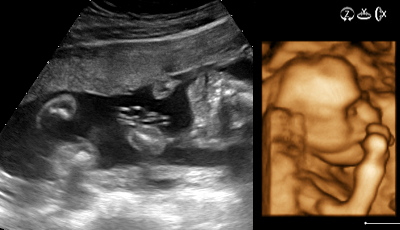

La vita stupisce. Ho già avuto la gioia della paternità e di vedere crescere - e farsi ragazzini - i due neonati che ho visto nascere con emozione, assistendo ai parti come di prammatica per noi papà moderni. Una volta era una rarità e mio papà assistette ai parti dei suoi figli solo perché, come veterinario, era considerato un collega e, visto che gli piaceva scherzare, ricordo che una volta da bambino commentò con una persona che a curare i figli ci pensava lui perché eravamo due... asini. Ora, tra pochi mesi, avrò di nuovo questa gioia della nascita di un bimbo (maschietto, come si dice) e anche in questo caso, rispetto al passato, possiamo con gli ecografi di nuova generazione spiare l'"abitante", brillante definizione che un'amica ha dato di chi cresce nel ventre materno in attesa di avere un nome. Ogni volta, di fronte ad una nascita che verrà, ci si domanda se il mondo attuale sia il posto migliore dove accogliere il nascituro. Quando lo si percepisce come il frutto dell'amore, ogni dubbio è sbagliato. P.S.: saluto l'arrivo di Giulia e saluto con affetto mamma Elena e papà Angelo, che via sms - forza della tecnologia - mi ha annunciato nella notte il lieto evento!